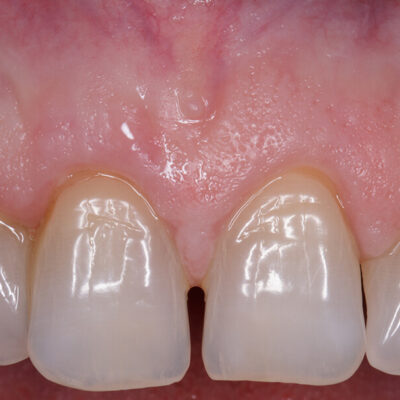

Canino superiore con recessione: prima e dopo Intervento di Chirurgia Mucogengivale con sostituti dermici

Quando le recessioni sono iniziali è sufficiente modificare le tecniche di spazzolamento e tenere le lesioni sotto controllo.

Quando iniziano a diventare un problema estetico, soprattutto nei denti anteriori , quando il paziente accusa molta sensibilità o i denti tendono a cariarsi sulla porzione di radice scoperta la Chirurgia Mucogengivale è in grado di riportare le gengive a dei livelli corretti.

La tecnica chirurgica prevede spesso il prelievo di una porzione di mucosa prelevata dal palato che andrà inserita nella zona della recessione gengivali. Questo normalmente causa un notevole fastidio al paziente nella zona di prelievo dal palato.

Da più di 15 anni la ricerca sui biomateriali ha messo a disposizione degli ottimi sostituti connettivali che evitano il prelievo di connettivo dal palato.

Per il trattamento chirurgico di circa 1.500 recessioni gengivali il dr. Patarino Domenico ha sempre utilizzato i biomateriali sostituti dermici, evitando il prelievo dal palato, con ottimi risultati clinici, evitando le complicanze possibili di questo intervento e diminuendo di molto il dolore e il gonfiore post-operatorio dei suoi pazienti.